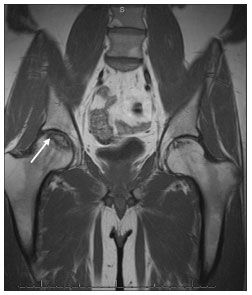

Figure 3.MRI of the pelvis with the "double line" sign (arrow) characterized by a high-intensity signal inside a low-intensity peripheral rim indicating osteonecrosis. Note the development of bilateral hip osteonecrosis in this patient.

He has had mild, intermittent right hip discomfort for the past 6 months. Findings from previous physical examinations were unrevealing, and he retained full mechanical function, initially prompting conservative treatment with anti-inflammatory medication. A heel lift was placed in his right shoe, which offered mild relief. However, his symptoms progressed to a deep, throbbing pain radiating to his right groin, which worsened with weight-bearing activity. Plain radiographs followed by MRI of his pelvis confirmed the diagnosis of osteonecrosis (Figures 1, 2, and 3). He underwent total hip arthroplasty, with complete resolution of his symptoms.